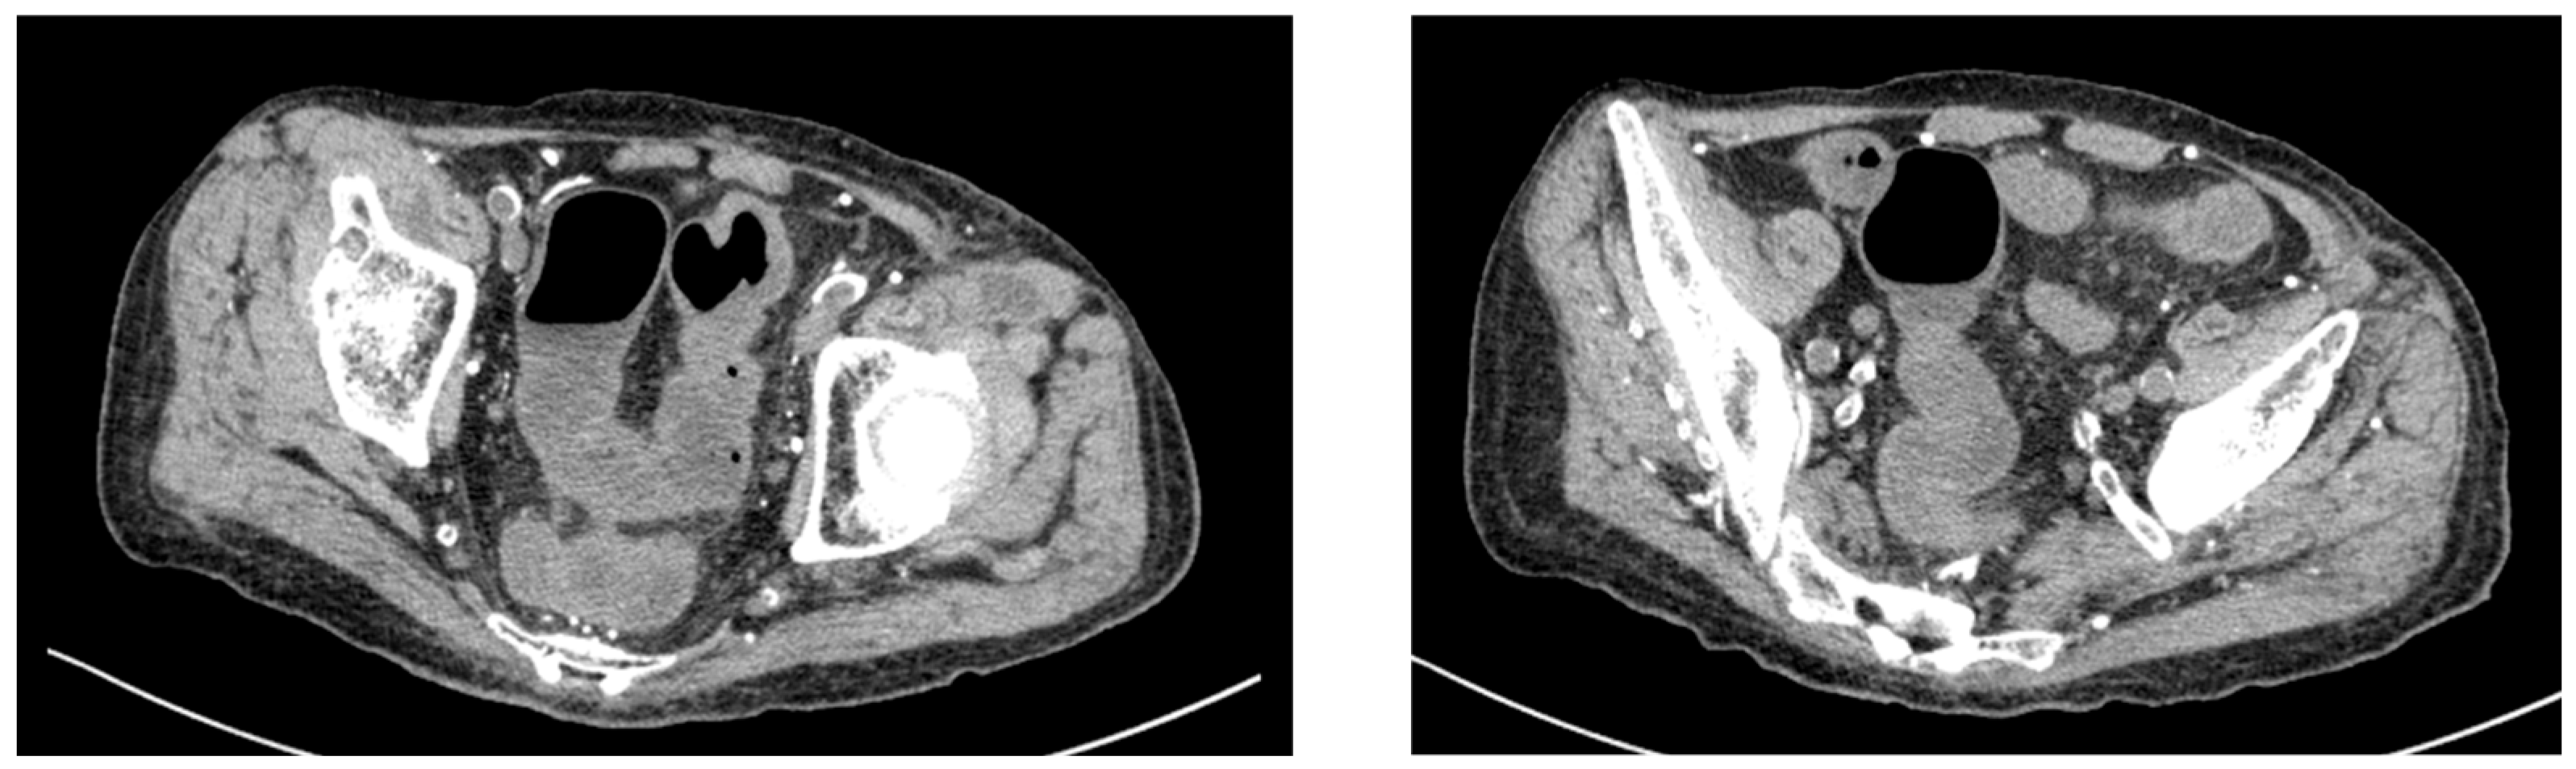

Given his renal impairment and dialysis dependence, paclitaxel was initiated at a reduced dose of 60% of the standard dose. On day 16 of paclitaxel treatment, the patient experienced severe diarrhea with 10 episodes per day and presented to the emergency department. Computed tomography of the abdomen revealed findings consistent with colitis (Figure 2). Laboratory investigations showed inflammatory changes (Table 1). The patient was admitted for further evaluation and management.

Figure 2. Abdominal computed tomography findings at emergency department presentation. The CT scan demonstrates thickening of the colonic wall.